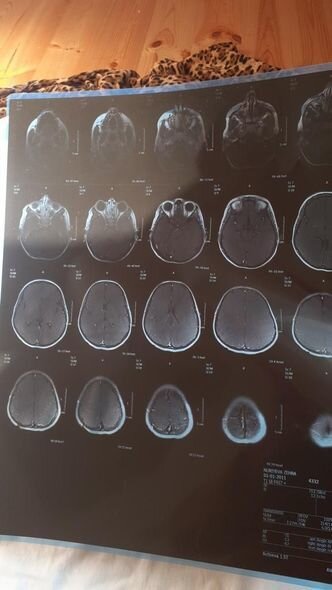

12 yaşlı Zəhra iki ağır xəstəliklə mübarizə aparır.

O qeyd edib ki, övladı Zəhra Hüccət qızı Nuriyeva həm autizmdən, həm də serebral iflicdən əziyyət çəkir:

"Biz Lənkəranda yaşayırıq. Beş övladım var. Onlardan ən böyüyü Zəhradır. Onun iki ağır xəstəliklə mübarizəsi, həqiqətən, bir ana olaraq məni məhv edir. Qızımın vəziyyəti günü-gündən ağırlaşır. Bir neçə aydır müalicələrini etdirə bilmədiyimiz üçün vəziyyəti lap pisləşib. Zəhranın gün ərzində 4-5 dəfə epilepsiyası tutur. Hər dəfə onu geri qaytara bilməyəcəyəm deyə qorxudan az qalıram dəli olam. Yardımsevər şəxslərdən mənim övladıma dəstək olmalarını, onun əlindən tutmalarını xahiş edirəm. Müalicə üçün hazırda 1 000 manata ehtiyacımız var".